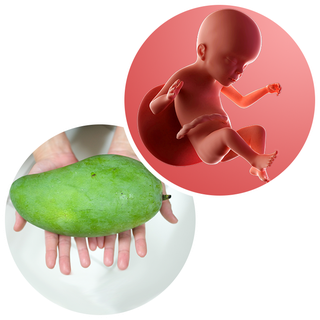

Your baby, or foetus, is around 28.9cm long from head to heel. That's approximately the size of a large mango.

Your baby's limbs are now in proportion. Over the next few weeks, you're going to be kicked around by your baby and will start to see your tummy move too, which looks very strange.